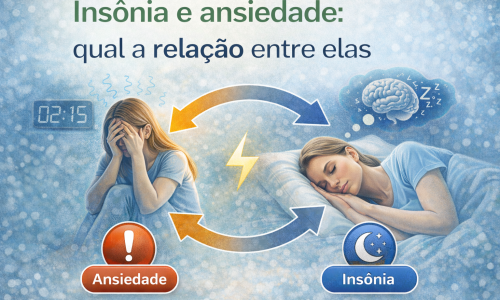

Estudos científicos indicam que o sistema endocanabinoide participa da modulação da dor muscular e articular, além de influenciar processos inflamatórios locais e a resposta ao estresse, fatores diretamente relacionados à disfunção temporomandibular.

Além disso, quadros crônicos de DTM frequentemente apresentam envolvimento de mecanismos de sensibilização central, o que pode dificultar a resposta a terapias convencionais isoladas. Nesses casos, estratégias terapêuticas complementares voltadas à modulação da dor e da inflamação vêm sendo estudadas como parte de um plano clínico individualizado e multidisciplinar.